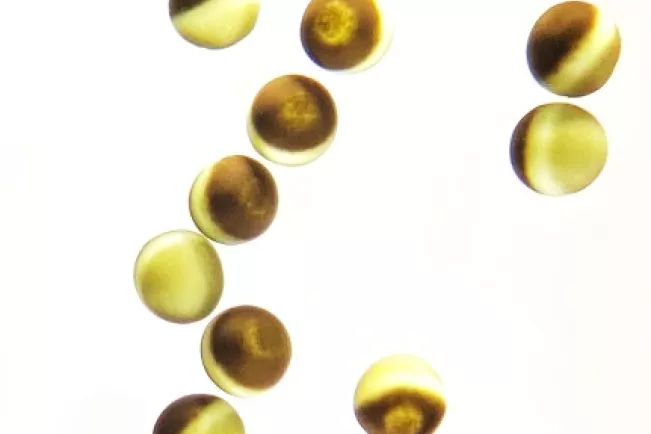

Das Gerät basiert auf der sogenannten Xenopus-Oozyten-Expression zur Messung der Aktivität von Transportproteinen. Xenopus Oozyten sind ein weltweit etabliertes zelluläres Modellsystem und sie eignen sich durch ihre hohe translationale Kapazität und geringe endogene Ausstattung an Transportproteinen als hervorragendes System zur Expression und funktionalen Charakterisierung von Ionenkanälen/Transportern. Dazu wird RNA, welche für das zu charakterisierende Transportprotein kodiert, mittels Mikroinjektion in die Zellen eingebracht. Nach einer Inkubationszeit von wenigen Tagen, kann anschließend die Aktivität der von der Zelle hergestellten Transportproteine mittels elektrophysiologischer Ableitungen (Two-Electrode Voltage-Clamp) gemessen werden. Durch den Einsatz des Gerätes können bislang unbekannte Transportproteine charakterisiert werden, Auswirkungen von DNA-Varianten auf die Funktion von Transportproteinen erforscht werden, Struktur-Funktions-Analysen an Transportproteinen durchgeführt werden, sowie neue Wirkstoffe entwickelt und pharmakologisch charakterisiert werden.